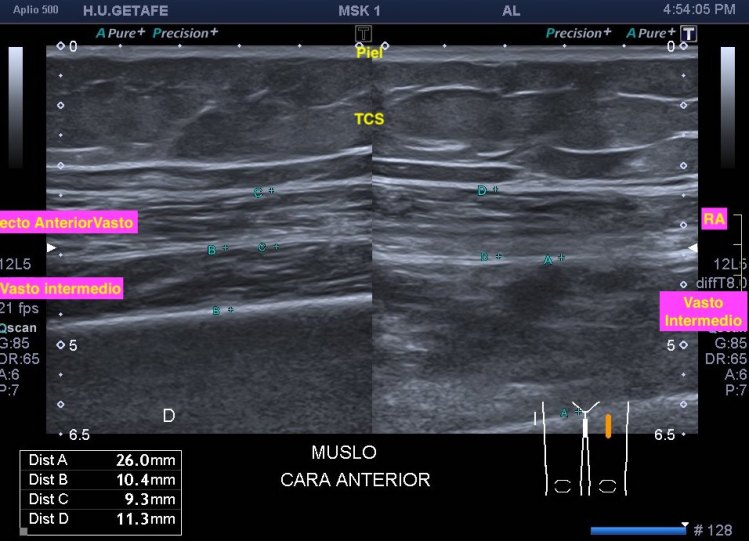

Me llama poderosamente la atención, lo recuerdo perfectamente, la normalidad del recto anterior, pero después de buscar un poco observo como el vasto intermedio si está «distinto», algo heterogéneo, voy a comparar con el lado contralateral y bingo¡ el vasto intermedio, que es de esa musculatura «que nunca tiene nada», modo «ironía on», te sorprende…y la ecografía muscular es como el océano, nunca puedes confiarte…

Mira las imágenes y tu misma te darás cuenta:

La zona que presenta mayor abombamiento y empastamiento (cara lateral del muslo izquierdo), se visualiza aumento del grosor del fascículo muscular correspondiente con el vasto intermedio, sin poder evidenciarse la presencia de lesiones definidas. El diagnóstico es un aumento difuso e inespecífico del Vasto Intermedio, sin masas ni roturas. A valorar con RMN.